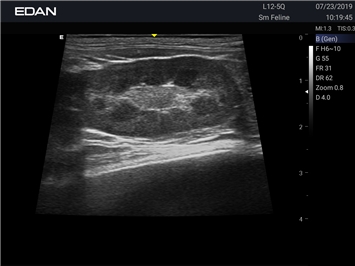

Новая эра УЗИ в ветеринарии. Диагностическая ультразвуковая система для ветеринарии, AX8 — это многофункциональная диагностическая ультразвуковая платформа с расширенными режимами визуализации, двумя сенсорными экранами с жестовым управлением и полным набором датчиков, которые соответствуют конкретным потребностям ветеринаров.

Профессиональный ветеринарный УЗИ аппарат EDAN Acclarix AX8 VET сочетает инновационные технологии визуализации с надежной конструкцией, специально разработанной для ветеринарной практики.

Передовые технологии визуализации

Высокая точность диагностики:

• Многоканальная аппаратная платформа обеспечивает исключительное качество изображений

• Технология адаптивной визуализации тканей с автоматической оптимизацией

• Расширенные режимы визуализации для различных видов исследований

• Специализированные предустановки для ветеринарной диагностики